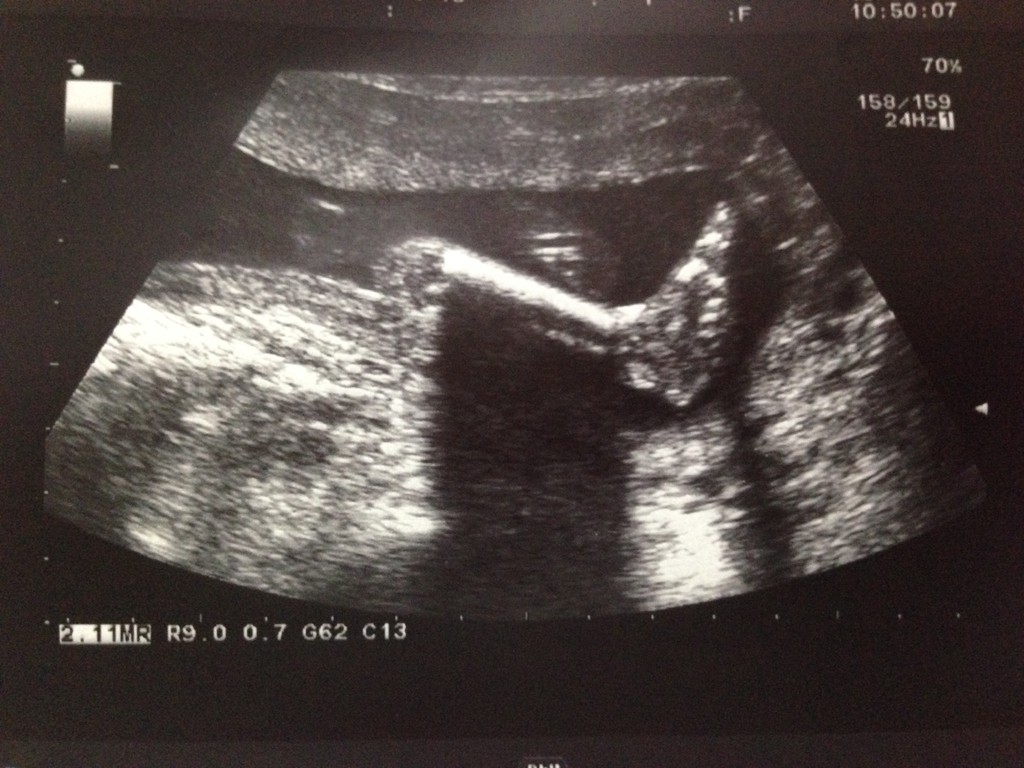

21W2D蹦蹦骨:5.4cm,咪重:53.8kg

的蹦蹦:

好,羊膜穿刺告!幸好告查都正常!

咪安心多了~~告染色也了你是妹妹,